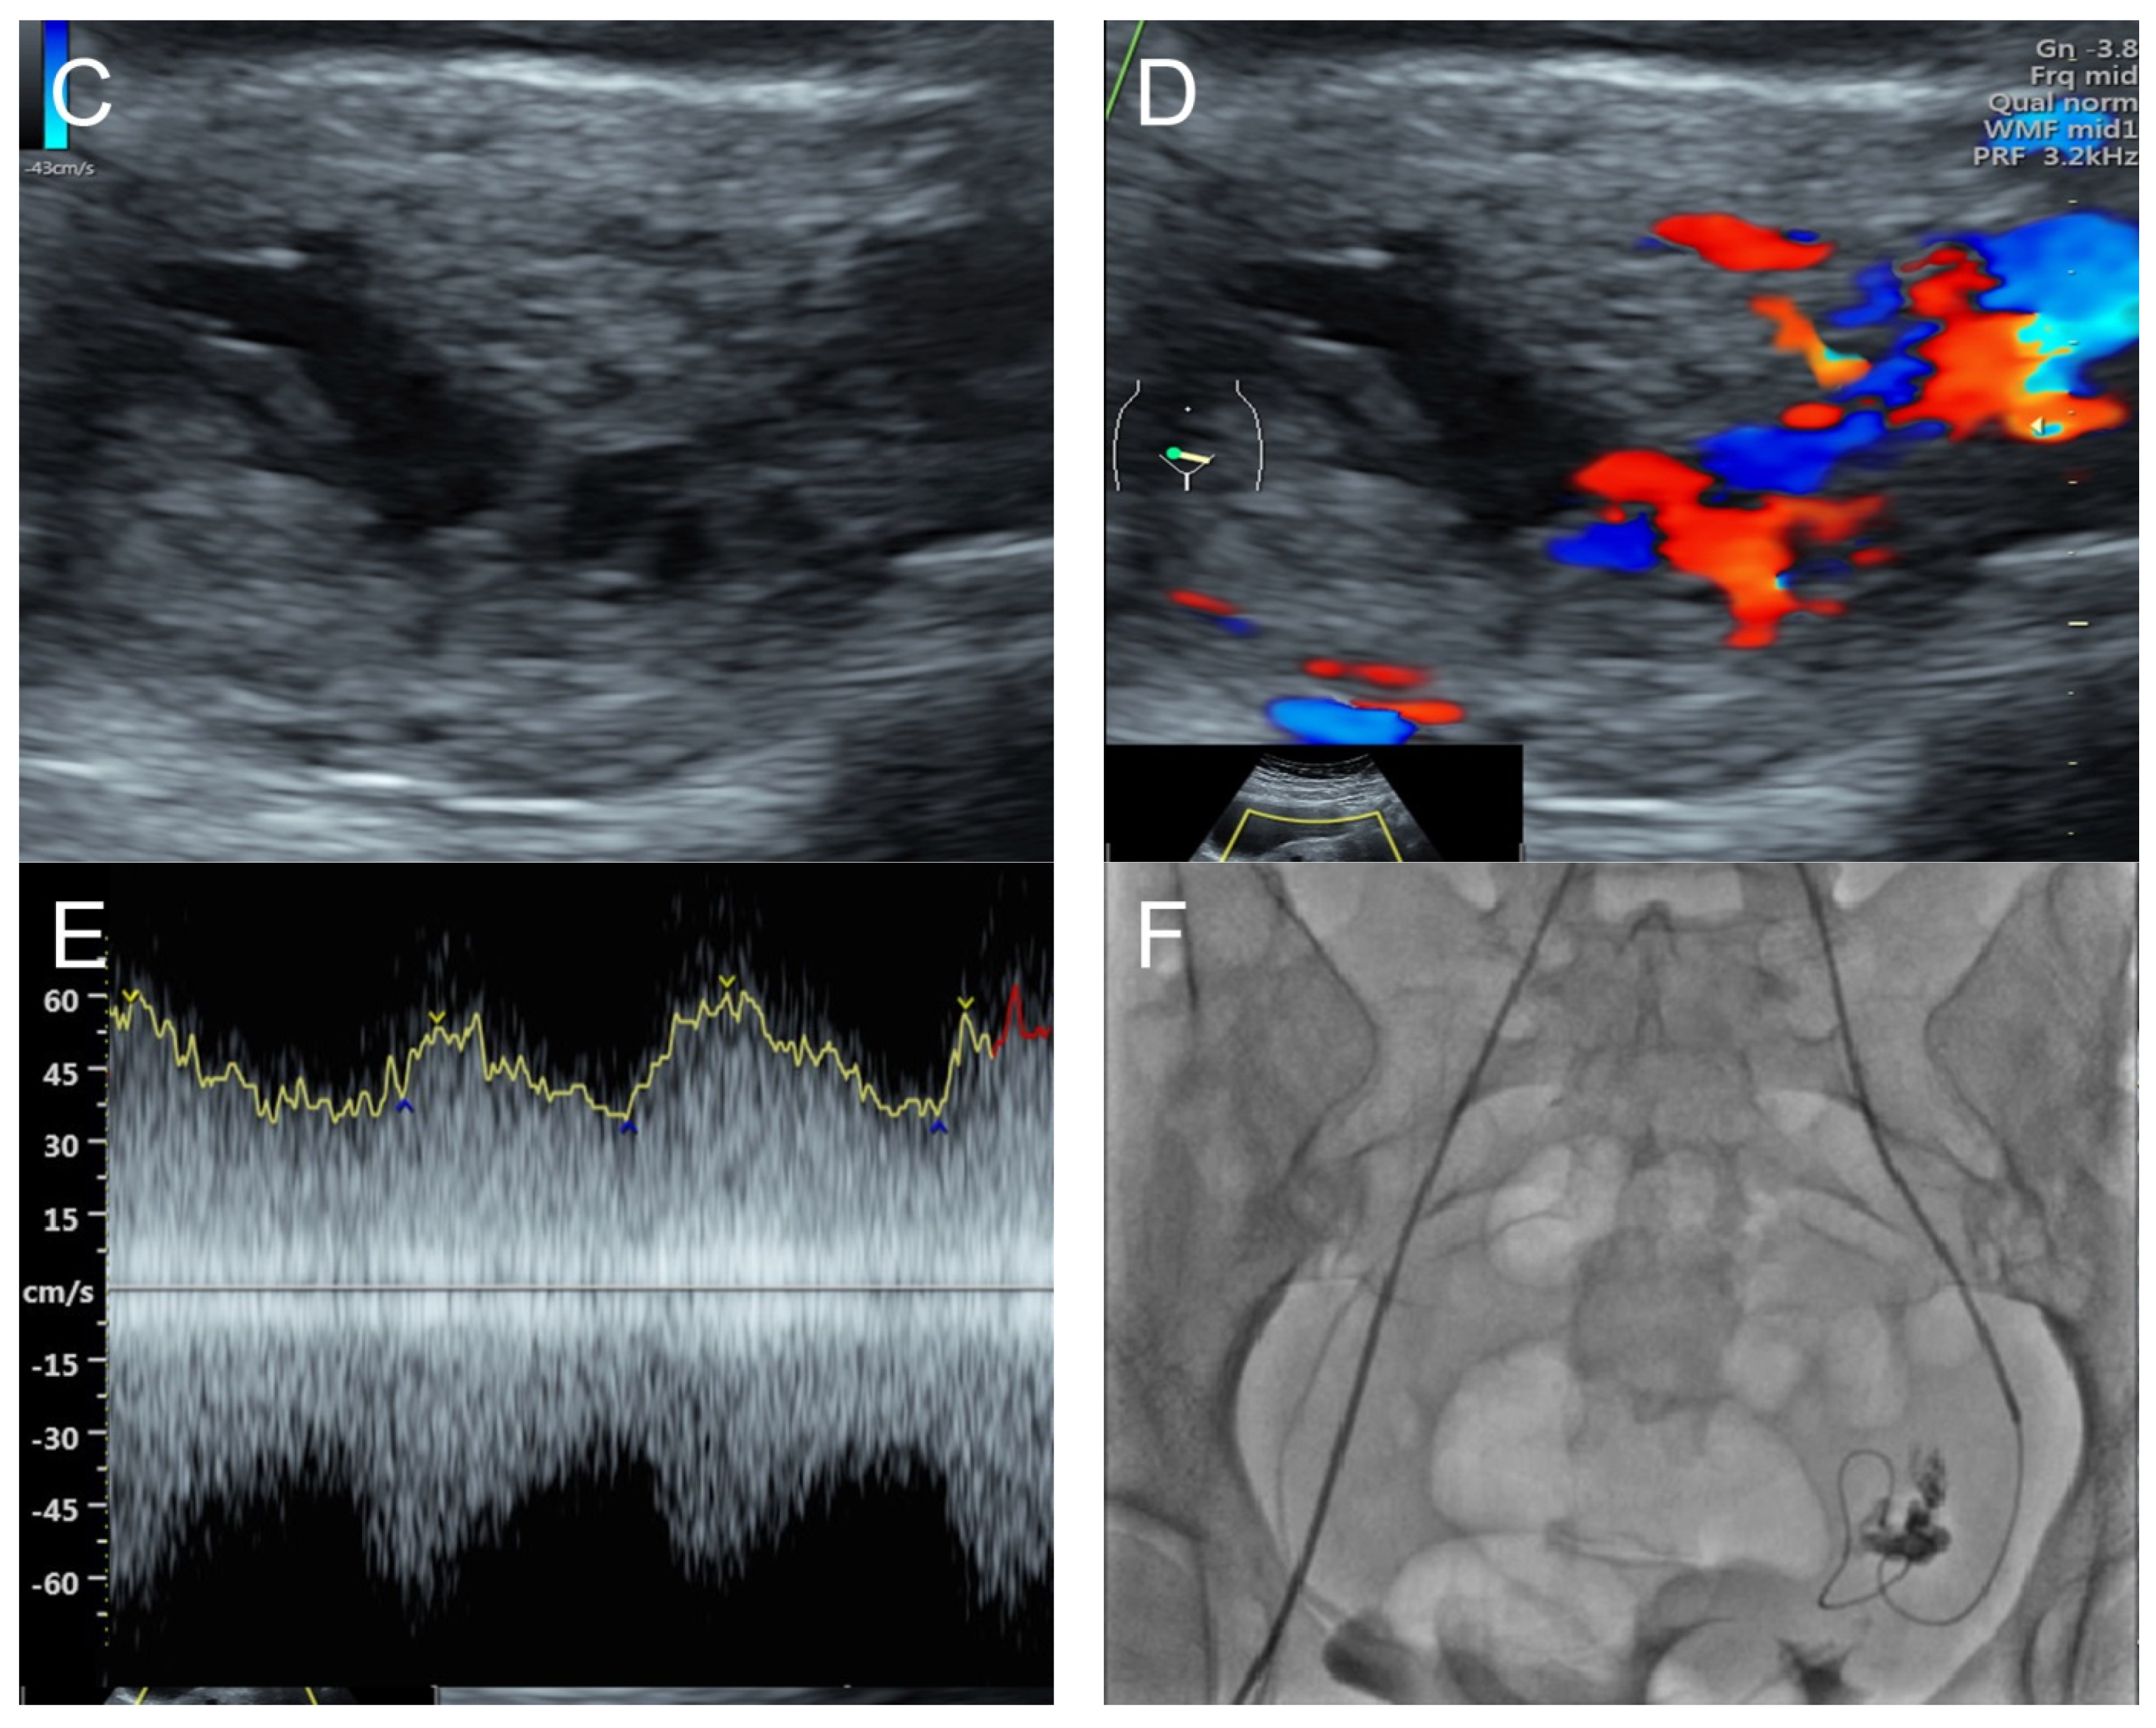

6. Case 5 (Figure 5)

Figure 5. (A,B) Transvaginal ultrasound: sagittal scans of the uterus showed several small anechoic/hypoechoic cysts, giving a spongy pattern and varying in size, throughout the myometrium; no other specific lesions of the uterus. The uterine cavity was lined with a thin endometrium and filled with anechoic fluid, probably lysed blood. (C) Color flow mapping showed hyper-vascularization in the cystic spaces, as seen in figure (A,B), throughout the myometrium and a multidirectional chaotic flow. The main differential diagnosis was adenomyosis or gestational trophoblastic disease. (D) Spectral Doppler showed a high peak systolic velocity (~70 cm/s) with a low resistance index of 0.2.

Management: Initial therapy included fluid resuscitation, blood transfusion, trans-rectal misoprostol at 800 mg, and intrauterine tamponade with a Foley catheter balloon, resulting in a reduction in bleeding, but significant bleeding still persisted. A transabdominal total hysterectomy was successfully performed, with satisfactory outcomes. The operative findings and pathological examination confirmed the diagnosis of uterine AVM. The patient was healthy and asymptomatic at the 6-week post-operative check-up. However, unfortunately, she was lost to follow-up after this point.